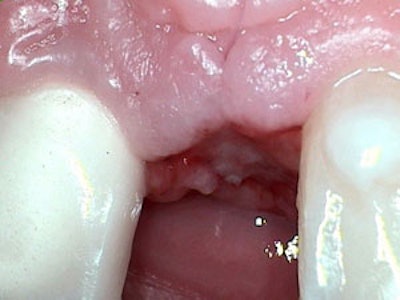

Top: Dr. Hatch after the extraction and before the implant placement. Bottom: One week after the extraction, bone graft, and implant placement. "Things are healing well, and I got my new fake tooth," Dr. Hatch said.

A week afterward the procedure, he took a post-op picture and posted it on his Facebook page. "It's looking good!" Dr. Hatch said. "I just have to let it heal for a couple more months, and then we'll put a tooth on it."